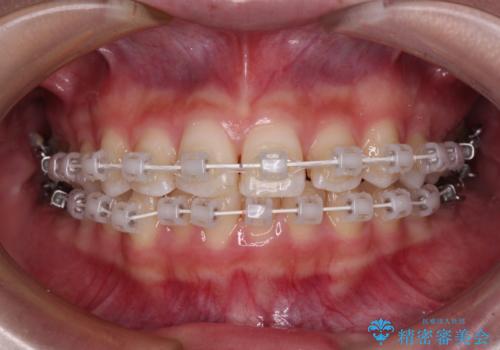

- 矯正装置

- 審美装置

- 治療期間

- 10ヶ月

矯正治療は8ヶ月ほどで終了し、速やかに虫歯治療に移行することができました。